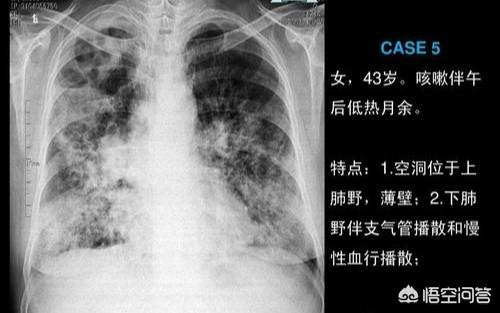

上图是一位肺结核患者的胸部x线图像,可以看到两肺弥漫性的结核感染灶。